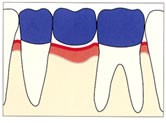

かみ合わせた状態 術後の右はレントゲン写真

かみ合わせた状態 術後の右はレントゲン写真